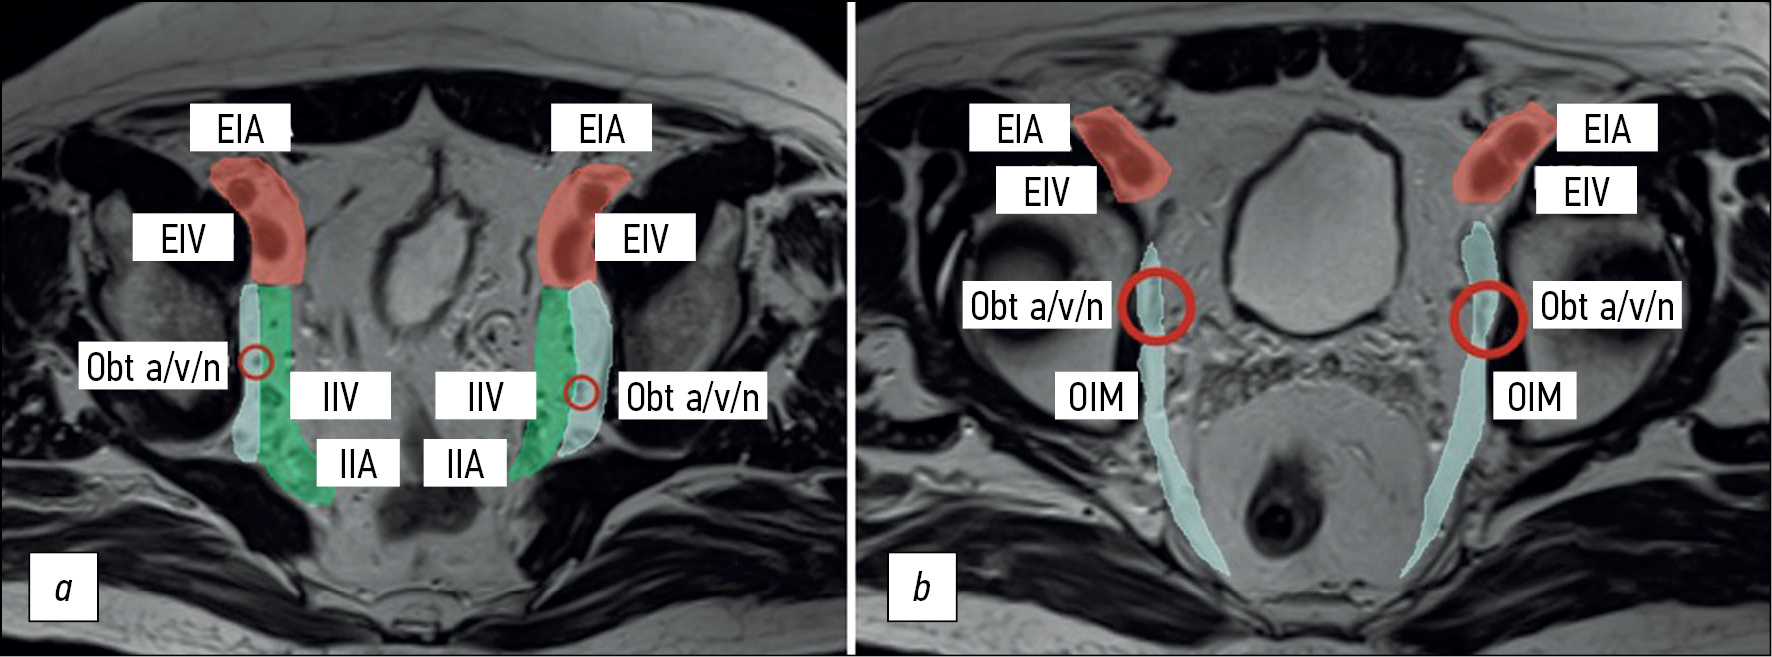

Not all lymph nodes located in the pelvis are regional for rectal cancer and are classified as “N.” When assessing pelvic lymph nodes as regional, it is important to consider their location (Fig. 4) and, if possible, indicate it in the examination report. Here are terms related to location, staging, and criteria for lymph node involvement.

The lateral pelvic lymph nodes, situated at the side pelvic walls, are lymph nodes external to the mesorectal fascia, including the external, internal iliac, and obturator lymph nodes. When describing them, it is better, whenever possible, to indicate a more specific location. During primary staging, it is recommended to consider regional lateral pelvic lymph nodes (internal iliac and obturator) with a short axis (≥7 mm) as suspicious [12, 27]. Morphological criteria for lateral pelvic lymph nodes are not recommended [13].

The internal iliac lymph nodes are regional and, in the case of rectal cancer, are included in the scope of dissection of the lateral pelvic lymph nodes. They are located along the internal iliac vessels. At the level of the obturator muscle, they are localized medially to the internal iliac artery; lymph nodes lateral to the internal iliac artery are considered obturator lymph nodes (Fig. 4).

Fig. 4. Localization of the lateral pelvic lymph nodes (colored): external iliac lymph nodes are red; obturator lymph nodes are blue; and internal iliac lymph nodes are green. Shown in levels (a) proximal and (b) distal. EIA: external iliac artery; EIV: external iliac vein; IIV: internal iliac vein; IIA: internal iliac artery; Obt a/v/n: obturator artery/vein/nerve; OIM: obturator internus muscle.

The obturator lymph nodes are regional. They are located between the external and internal iliac arteries, medially to the internal obturator muscle and laterally to the internal iliac artery (Fig. 4).

The external iliac lymph nodes are not regional. They are located along the external iliac vessels (Fig. 4) and are divided into lateral, middle/median, and medial chains. The lateral subgroup is located laterally to the external iliac artery. The middle/median group is between the artery and the vein. The medial group is posterior to the external iliac vein. The lymph nodes in the medial subgroup are located near the obturator vessels and obturator lymph nodes. This can cause diagnostic difficulties because they are often indistinguishable from the obturator lymph nodes localized along the obturator artery at the point of its origin from the internal iliac (hypogastric) artery at the level of the internal obturator muscles [3]. Involvement of the external iliac lymph nodes in rectal cancer is extremely rare. Non-regional lymph nodes are considered suspicious if they measure >10 mm in short axis.